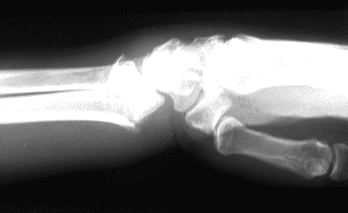

Case 2 Preop